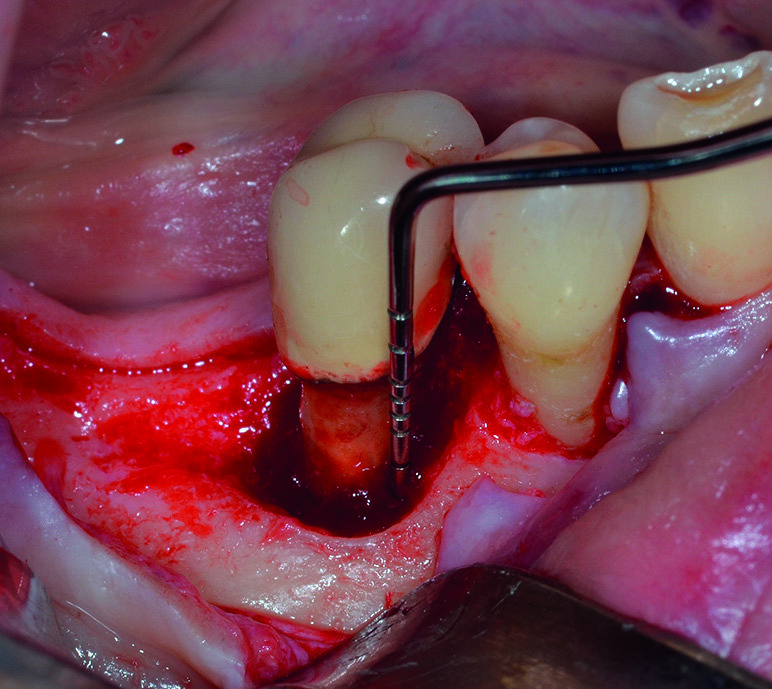

Dopo analgesia locale ottenuta per infiltrazione di Articaina cloridrato 40 mg con epinefrina 1:100.000 viene effettuata l’ incisione di accesso in accordo con il protocollo chirurgico sopra citato (Fig. 4). Al sollevamento del lembo è possibile evidenziare un profondo difetto che coinvolge l’aspetto disto-buccale dell’ elemento 4.5; con una sonda parodontale millimetrata di tipo Williams viene misurata la profondità della componente intraossea (Figg. 5-7). Il debridement della lesione e la decontaminazione della superficie radicolare vengono effettuati mediante una coppia di inserti dedicati montati su dispositivo ad ultrasuoni (ES030LDT ed ES030RDT, Esacrom Srl, Imola, Italia) (Fig. 8).